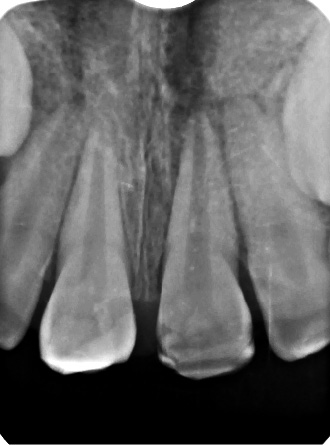

STRESZCZENIE: Artykuł przedstawia przypadek 8-letniego chłopca, u którego w wyniku intruzji zęba 21 doszło do powikłania pourazowego pod postacią resorpcji zewnętrznej korzenia. Poza efektami urazu, które uwidaczniają się natychmiast po jego wystąpieniu, nie należy zapominać o jego odległych skutkach, które również mogą zagrozić utrzymaniu zęba w jamie ustnej. W artykule opisano przebieg całego procesu leczenia oraz 12-miesięczne obserwacje radiologiczne.

SUMMARY: This article presents 8-years-old boy case, in which intrusion of tooth 21 resulted in external root resorption as a post-trauma complication. Despite the immediate effects of dental trauma we cannot forget about the distant complications, which may also affect tooth retention. This article describes the whole treatment process and 12-months radiological follow-up.